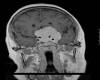

Se solicitó una resonancia nuclear magnética (RNM) con gadolinio urgente que mostró la presencia de un meningioma supra e infraselar de 5x4,3x4,8 cm sobre la silla turca, línea media cerebral anterior, alas menores del esfenoides y apófisis clinoides, con extensión hacia el seno cavernoso izquierdo y englobando la arteria carótida interna izquierda sin llegar a estenosarla, desplazamiento de la hipófisis y el hipotálamo, con un leve edema del lóbulo frontal (fig. 4). También presentó extensión hacia el ápex orbitario izquierdo a través de la fisura orbitaria, encontrándose el nervio óptico y su vaina engrosados y con signos de congestión venosa (fig. 5).

Fig. 4. RNM con gadolinio. Meningioma supra e infraselar de 5x4, 3x4,8 cm sobre la silla turca, línea media cerebral anterior, alas menores del esfenoides y apófisis clinoides, con extensión hacia el seno cavernoso izquierdo y englobando la arteria carótida interna izquierda, desplazamiento de la hipófisis y el hipotálamo, con un leve edema del lóbulo frontal.